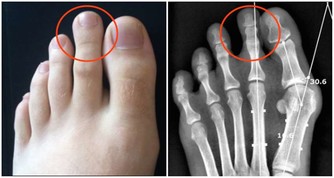

鼻子上出現這現象可能是胃癌我們都知道草莓鼻,非常影響美觀。

很多人都以為是皮膚問題,去美容院花上千元去除,但是效果並不好。

小編要提醒大家的是,草莓鼻並非一定是皮膚問題,也有可能是腸胃問題。

如果你發現鼻頭總是紅紅的,而且鼻頭上的毛孔也比較粗大,那麼你就要小心了,這可能是胃癌的先兆。

因為相關的研究發現鼻頭髮紅,或是鼻頭的毛孔粗大,

這很有可能是身體內部存在大量的幽門螺桿菌,這種病菌很有可能導致胃癌。

因此如果鼻頭髮紅或是毛孔粗大一定要及時去醫院做好檢查,以免延誤了病情。